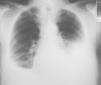

A los 2 meses acudió a control con disnea a moderados esfuerzos de reciente aparición y una radiografía que demostró la presencia de un derrame pleural bilateral. Ante la sospecha de una insuficiencia cardíaca se inició tratamiento con diuréticos, sin clara mejoría clínica o radiológica (fig. 1). Tras la persistencia de la misma disnea sin fiebre, dolor torácico o hemoptisis, se realizó una toracocentesis en ambos hemitórax. Se retiró el clopidogrel al observar unos líquidos pleurales claramente hemáticos (tabla I), y se mantuvo el tratamiento con ácido acetilsalicílico para evitar la oclusión del stent. La exploración física descartó la existencia de signos de insuficiencia cardíaca derecha, trombosis venosa profunda o adenopatías periféricas palpables. La auscultación cardíaca fue normal y en la respiratoria se observó una semiología de derrame pleural bilateral.

Fig. 1. Radiografía de tórax posteroanterior. Derrame pleural bilateral.